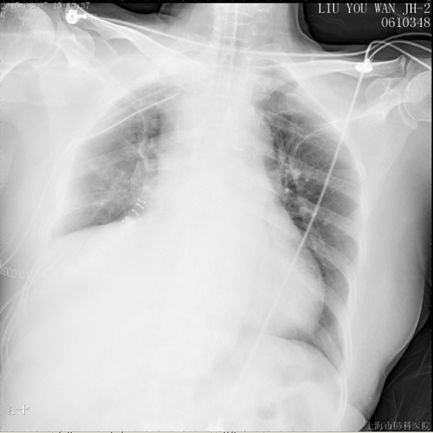

现病史:患者入院前体检发现右下肺占位28天,院外右下肺穿刺活检提示孤立性纤维性肿瘤,转入本院全麻下行心包内右肺中下叶切除和右胸腔肿块切除术,手术时间2.5h,术中失血100ml,无输血,术后病理显示梭形细胞肉瘤,倾向恶性孤立性纤维瘤,术后安返胸外科ICU,术后第一日胸引量350ml,无殊转回普通病房。次日凌晨患者下床如厕后突发胸闷气促,脸色苍白,四肢湿冷,无晕厥。面罩吸氧后仍诉胸闷气促无法缓解。心电监护:SPO2 70%,HR 100-120bpm,BP 110/80mmHg。实验室检查:血气分析:pH 7.16↓, PaCO2 56.5mmHg, PaO2 43mmHg↓, SpO2 62.2%↓。

初步治疗:吸氧;经鼻气管插管,机械通气;低分子肝素6000IU皮下注射;患者神志清,自诉症状未缓解,术后第二日予以转入ICU。转入ICU后予机械通气,Vt 480ml,FiO2 100%,HR 128bpm,SPO2和血压进行性下降,需血管活*药性**维持。